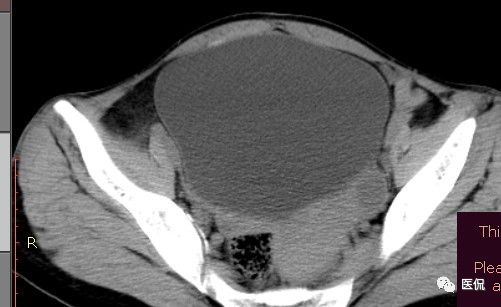

女 40岁 ,10年前做个剖腹产术。之后到现在一直感觉肚子疼,去很多医院做检查 诊断肠结核,经过反复抗结核治疗。病人10年瘦了几十斤。

腹腔内残留的纱布在人体内引起渗出或液化坏死并纤维包裹形成异物性脓肿(纱布瘤)。纱布瘤的影像特点:圆形或卵圆形肿块,较大,有完整包膜,薄壁,较少的情况下为厚壁,边界较完整,增强后薄膜可以持续强化。不同时期的纱布瘤可以有不同表现:早期(10个月或半年内)多表现为蜂窝状;2~5年内一般表现为囊性飘带状;10~20年之后则为实性软组织密度,包膜钙化呈钙化网状结构。手术过程中残留在人体内的医用纱布所形成的肿瘤样病变。